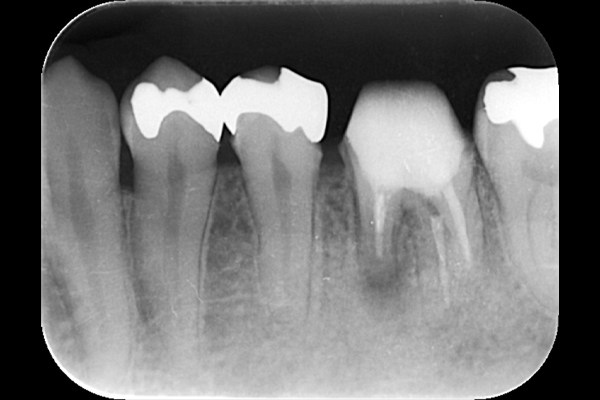

こちらは虫歯で神経を取らないといけなくなりましたが、何度治療しても痛みが消えないと言うことで当院にいらっしゃいました。度重なる治療で歯の神経のあった場所がかなりひろげられており、また根の先端も破壊されている状態でした。ですので、痛みが消えないのです。

肉眼では根の先端は見ることができませんがマイクロスコープでは見ることができます。根の先端をこれ以上破壊しないように清掃して歯の神経があった場所にお薬を詰めることができました。根の治療後、かぶせ物までして半年たっても痛みがありません。

レントゲンを見ていただいて、歯の先までしっかり白いお薬が入っているのがわかります。